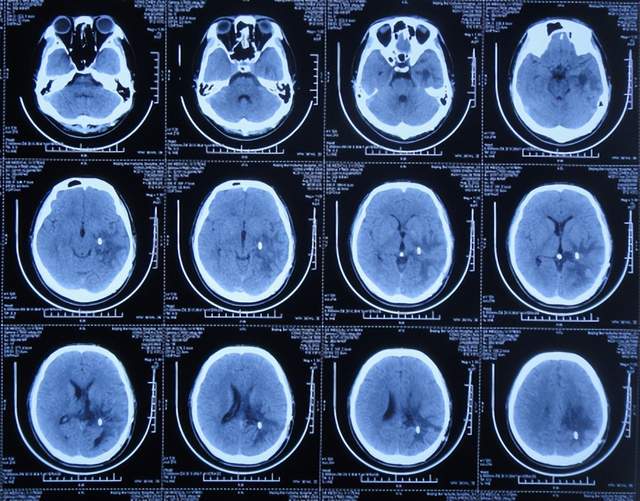

第2次出院后5个月即2022年6月初,再次出现头痛的症状,因左侧颞角再次增大,于2022年7月18日,第3次来到李小勇脑脊液科治疗。入院时:仅时有头痛。查头颅CT示左侧颞角扩张(图-33)。

图-33:2022年7月18日头颅CT

入院后3天即2022年7月21日,显微镜下颞角脉络丛切除术+分流管调整术,留置引流一根;术后查头颅CT示脑室内有2根管(图-34)。

图-34:2022年7月21日头颅CT

入院后11天即2022年7月29日(脉络丛切除术后8天),查头颅CT示引流术后状态(图-35)。

图-35:2022年7月29日头颅CT

入院治疗12天即2022年7月30日(脉络丛切除术后9天),给予拔除了原脑室腹腔分流管,查头颅CT示脑室内有一根管(图-36)。

图-36:2022年7月30日头颅CT

入院治疗21天即2022年8月8日(脉络丛切除术后18天),查头颅CT未见异常(图-37),患者身体无异常(图-38)。

图-37:2022年8月8日头颅CT

2022年8月22日(脉络丛切除术后32天),查头颅CT示颞角未见扩张(图-39),给予夹闭引流管。

图-39:2022年8月22日头颅CT

夹闭引流管14天后即2022年9月5日(脉络丛切除术后46天),查头颅CT示未见异常(图-40)。

图-40:2022年9月5日头颅CT

夹闭引流管15天后即2022年9月6日(脉络丛切除术后47天),给予拔除了脑室外引流管,当天查头颅CT示脑室基本正常(图-41);患者身体无异常。

图-41:2022年9月6日头颅CT

拔除了脑室外引流管后6天即2022年9月12日, 查头颅CT示未见异常(图-42);身体一切正常,于2022年9月16日出院。

图-42:2022年9月12日头颅CT

出院后3个月即2022年11月,在当地医院查头颅CT示无异常(图-43);本人叙述身体一切正常。

图-43:2022年11月头颅CT